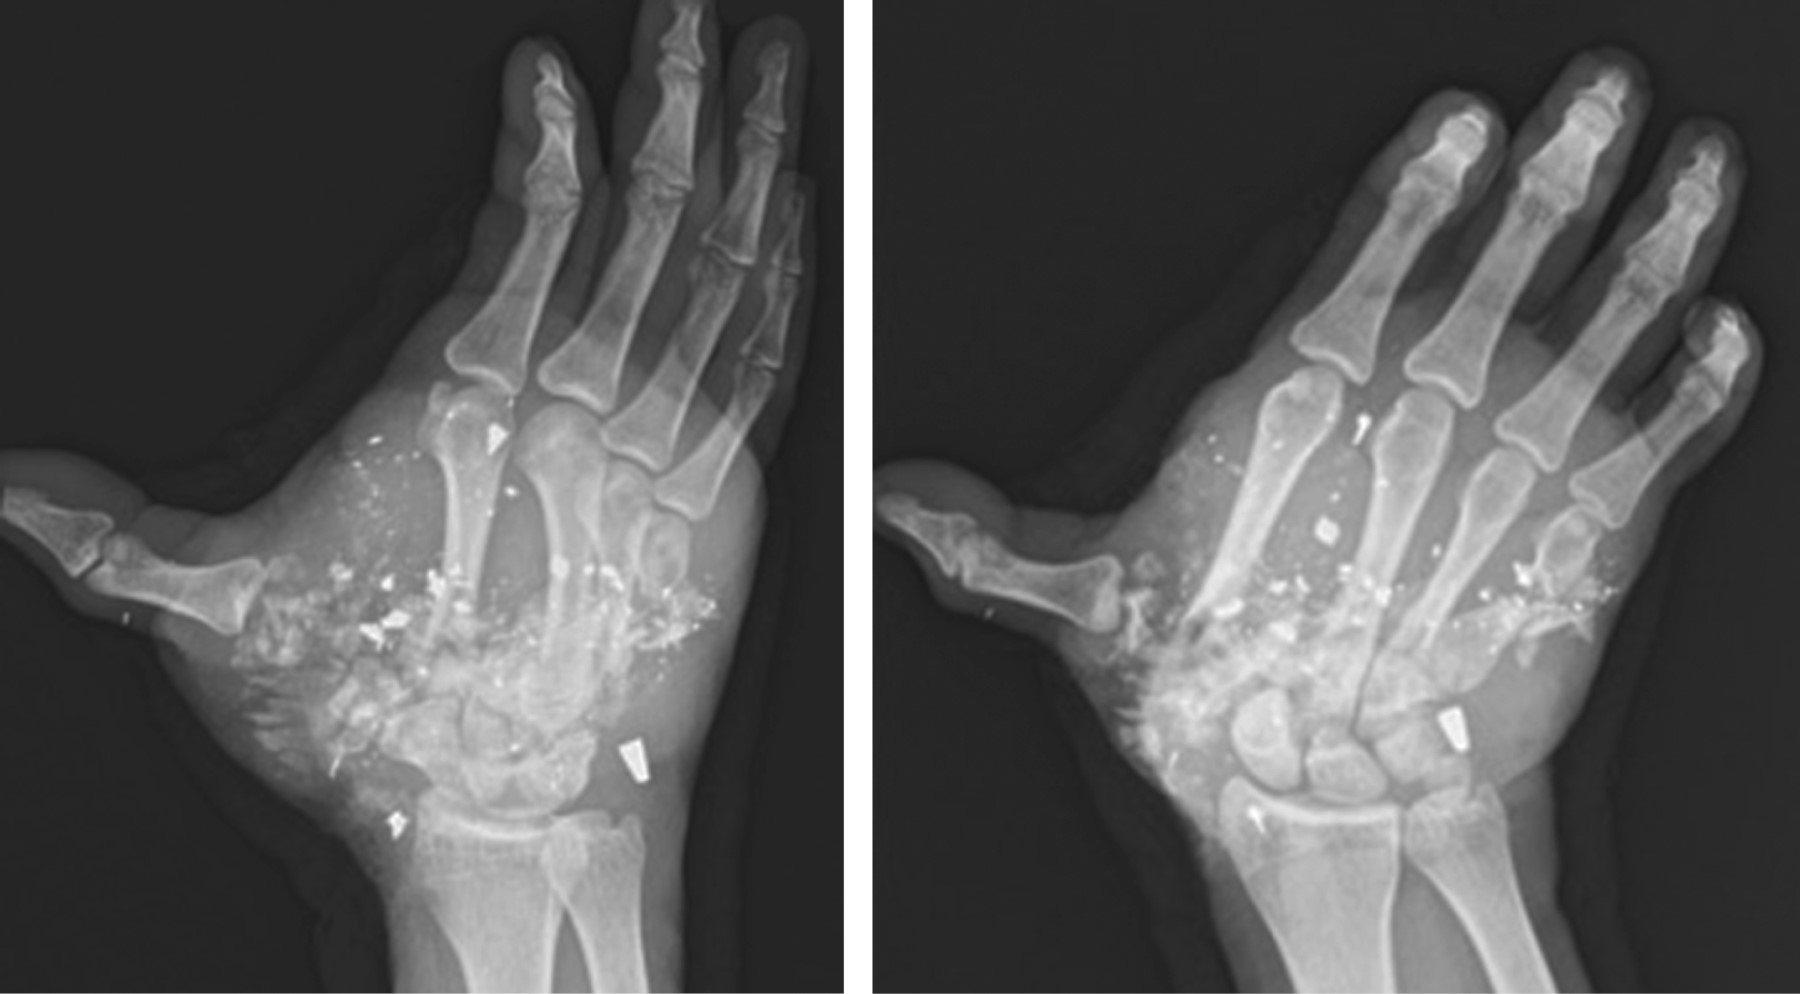

Free flaps for traumatic hand reconstruction due to gunshot injury; case report and literature review

Gunshot wounds cause about 15% of open fractures admitted in a hospital in border cities, up to half of these are serious injuries with a high incidence of skin and bone loss, and in severe cases with vascular damage. We report the case of a patient with traumatic hand injury secondary to a gunshot wound with a radial artery injury treated with a free radial contralateral forearm flap without success, subsequently an anterolateral thigh flap was performed with good outcomes for his social and labor reintegration.

Figure 2